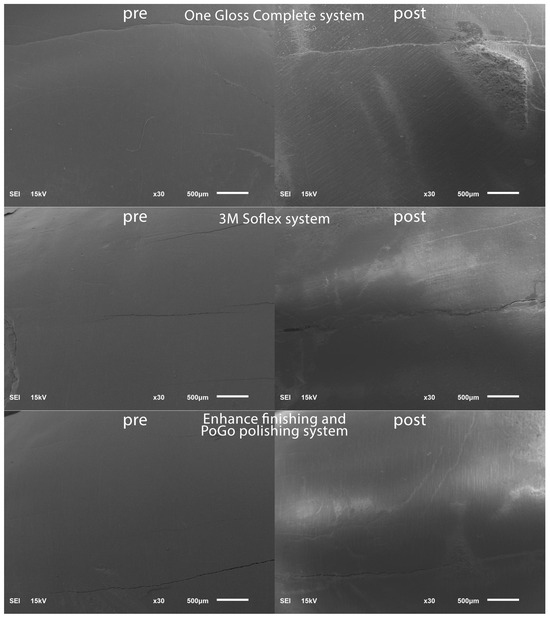

To establish a baseline for the surface roughness data, the teeth were positioned within a vinyl polysiloxane putty mold in preparation for scanning using a scanning electron microscope (SEM) (JSM 6610LV; Jeol, Tokyo, Japan). The SEM parameters employed included 15 kV voltage and a 10 mm working distance. To highlight specific regions of interest on the facial tooth surface, magnifications of 30× were chosen and representative SEM scans were captured in the pre-bracket bonding state; see Figure 1.

Figure 1.

SEM images pre-bracket bonding and post-bracket debonding.

Post-residual cement removal, enamel roughness measurements were performed in a similar routine to the pre-operative enamel surface roughness measurements and representative SEM scans were captured post-bracket debonding; see Figure 1.